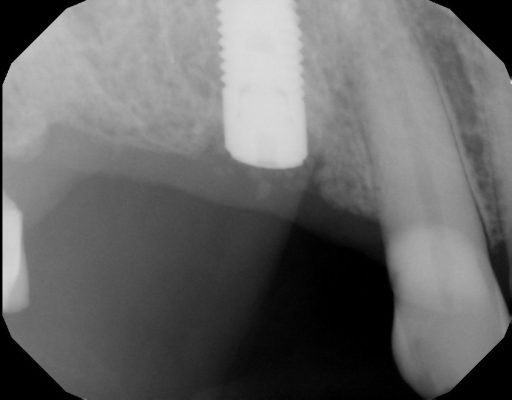

Hey guys just wanted to get to know your thoughts on what I can do to improve. This is a 78 yr old patient with controlled diabetes/hypothyroid/high BP. She takes her medications regularly and reports to be controlled. #29 was extracted due to fracture in October 2022 with bone graft. Implant Astra Osseospeed EV size 3.6×9 was placed in…

I created a deeper osteotomy today and placed a larger longer implant after removing the failed implant and thoroughly curetting and irrigating with CHX. Any guidance and feedback is welcome.